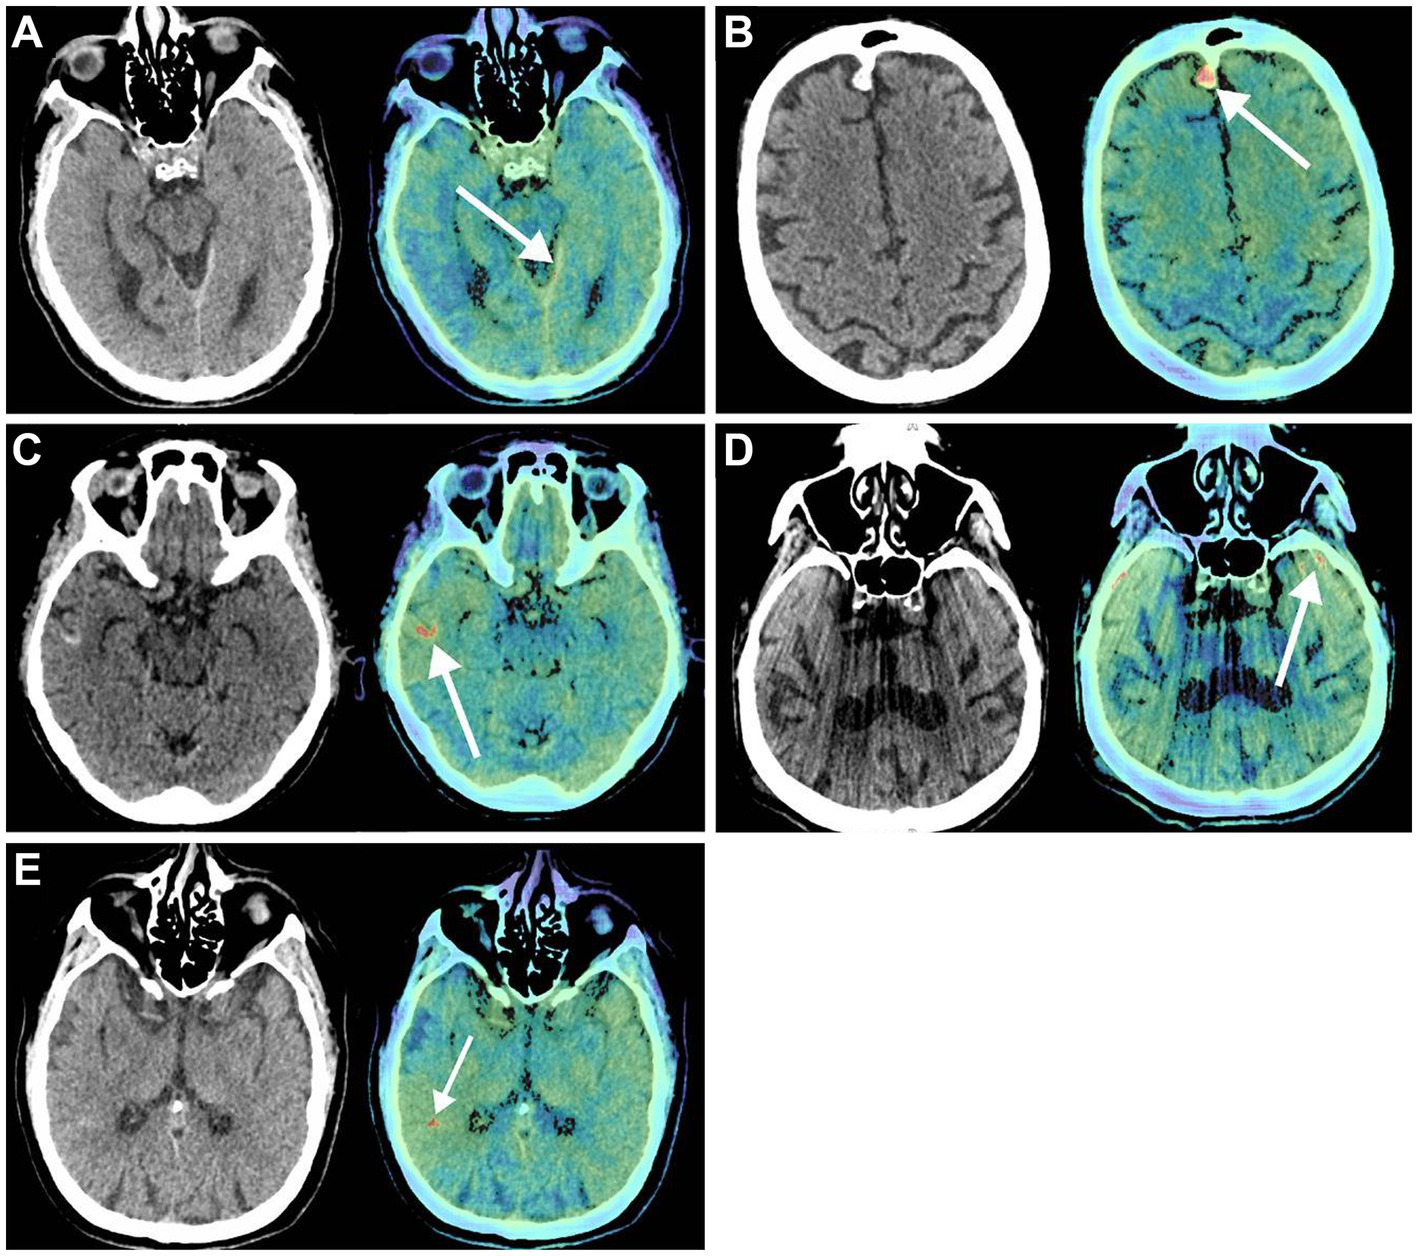

Previously, the diagnostic accuracy of ICHs using DL models was tested in a retrospective study by Voter et al. (38). This study used a US Food and Drug Administration–approved DL model, Aidoc, to assess the diagnostic accuracy of ICHs using 3,605 noncontrast CT of adults (Figure 4). This study showed a decreased sensitivity and positive predictive value of the model compared to their expectations and previous studies, with specific patient features such as previous neurosurgery, hemorrhage type, and number of hemorrhages further reducing diagnostic accuracy. The authors raised concerns regarding the generalizability of these DL models. They additionally stressed the need to include patients with a prior history of a neurosurgical procedure when training these models and a more stringent standardization of study parameters in future studies (38).

Figure 4

Deep learning (DL) in diagnostic support in neurosurgery. Voter et al. (38) focused on the application of a US Food and Drug Administration–approved DL, Aidoc, to determine its ability to recognize intracranial hemorrhages on noncontrast computed tomography (CT) accurately. Noncontrast CT (left) and the key images (right) in which the Aidoc identified the pathology (white arrows). (A) True positive finding in which the intracranial hemorrhage was not identified by the neuroradiologist. (B) Image of a meningioma that was incorrectly identified as an intracranial hemorrhage by Aidoc. (C) Cortical laminar necrosis incorrectly identified as an intracranial hemorrhage by Aidoc. (D) An artifact misidentified by the Aidoc. (E) Failure mode with the absence of a clear pathology. Used with permission from Voter AF, Meram E, Garrett JW, Yu JJ. Diagnostic Accuracy and Failure Mode Analysis of a Deep Learning Algorithm for the Detection of Intracranial Hemorrhage. J Am Coll Radiol. 2021 Aug;18 (8):1143–1,152. Doi:10.1016/j.jacr.2021.03.005. Epub 2021 Apr 3. PMID: 33819478; PMCID: PMC8349782.